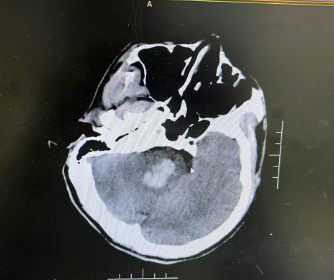

入院查体显示,患者已陷入昏迷状态,受到刺痛时无法睁眼、无法发音,肢体仅能做出屈曲反应,双侧瞳孔直径约2.5mm,对光反射存在,双侧肢体肌力约4级。紧急完善颅脑CT检查后,明确诊断为“脑干出血(脑桥)”,生命中枢遭受压迫,病情危急,随时可能进一步恶化!

孟娜副主任医师立即向科室主任侯鹏志汇报,侯主任仔细研读CT影像、分析病例,结合患者年龄、出血量及病情进展,果断判断:患者手术指征明确,决定急症行神经导航下脑内血肿清除+脑室穿刺外引流术清除颅内血肿、解除脑干压迫,才能为生命争取生机。

术前,团队快速完善CTA等辅助检查,全面排查动脉瘤等其他出血诱因,精准评估病情。术中,侯鹏志主任带领团队,依托神经导航系统这台“精准导航仪”,精准定位血肿位置,精心选取最优手术入路,全程毫米级操控,将手术切口控制在4厘米,最大限度减少对周围正常脑组织的损伤,顺利完成手术。术后患者生命体征平稳,清除血肿,神经功能逐步改善,为后续康复筑牢关键基础。